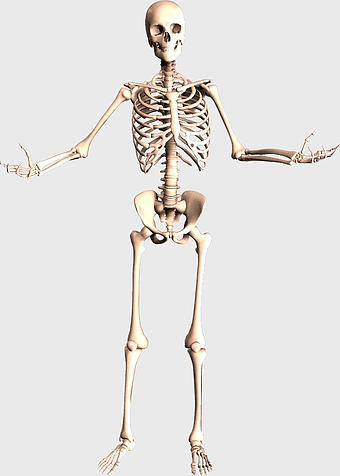

Human skeleton, rib cage anatomy, upper limb bones, joints in human body, skeletal structure analysis, vertebral column details, anatomical illustration study -

human skeleton illustration, skeletal system anatomy, axial skeleton structure, appendicular skeleton bones, human skeletal framework, skeletal joint connections, bone structure analysis -